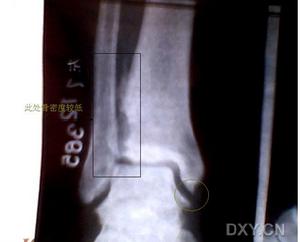

踝關節骨折的類型及移位形式很複雜,僅憑X線片很難對骨折的特徵進行全面的診斷分析,特別是後踝部分更為困難。憑藉CT平掃的圖像也難以從整體上認識踝關節骨折。螺鏇CT及三維重建技術能夠立體、直觀地顯示骨折的特徵,使臨床醫生可以在三維立體空間對骨折有全面的認識,它可以準確地顯示內、外及後踝的骨折類型及移位情況,指導臨床醫生制定出周密詳細的手術方案,因此在踝關節骨折的診治方面具有很大的優越性。本組1例患者的X線片提示內踝骨折,從螺鏇CT及三維重建的圖像上分析,其實僅為內踝的後丘部骨折,而前丘部完整、無骨折,我們對該患者採用踝關節的後內側入路的內踝復位及固定術。若無螺鏇CT及三維重建的資料,採用常規的前內側入路必然會使術中顯露及內固定的難度增加。脛骨前結節的撕脫性骨折即Tillaux骨折,在踝關節的正、側位X線片上很難被發現,而CT平掃的圖像又缺乏對骨折塊大小及移位程度的全面顯示,螺鏇CT及三維重建圖像則很清楚地顯示骨折塊的大小及移位程度。對此類骨折的治療,一般觀點為行石膏固定6周即可。但我們認為,應該依照螺鏇CT及三維重建的資料確定治療方案。若骨折塊較大,移位明顯且經非手術治療復位失敗者,應考慮手術治療。

踝關節骨折中對後踝的處理是關鍵,一般認為,骨折塊超過脛骨下關節面20%~25%的後踝骨折需要手術治療。從本組螺鏇CT及三維重建的資料分析,後踝骨折既可以表現為一完整的骨折塊,又可以呈粉碎性。對於粉碎性骨折,採用加壓螺釘固定顯然是不合適的。另外,後踝骨折線並不一定完全與脛骨下端的冠狀面平行,故固定後踝骨折時,螺釘的進釘方向應以螺鏇CT和三維重建的資料為依據,這才有可能使加壓螺釘的進釘方向與骨折線的方向垂直。這些對後踝骨折的細微處理,若無螺鏇CT及三維重建的資料,單憑X線資料,很難制定出詳細正確的治療方案。